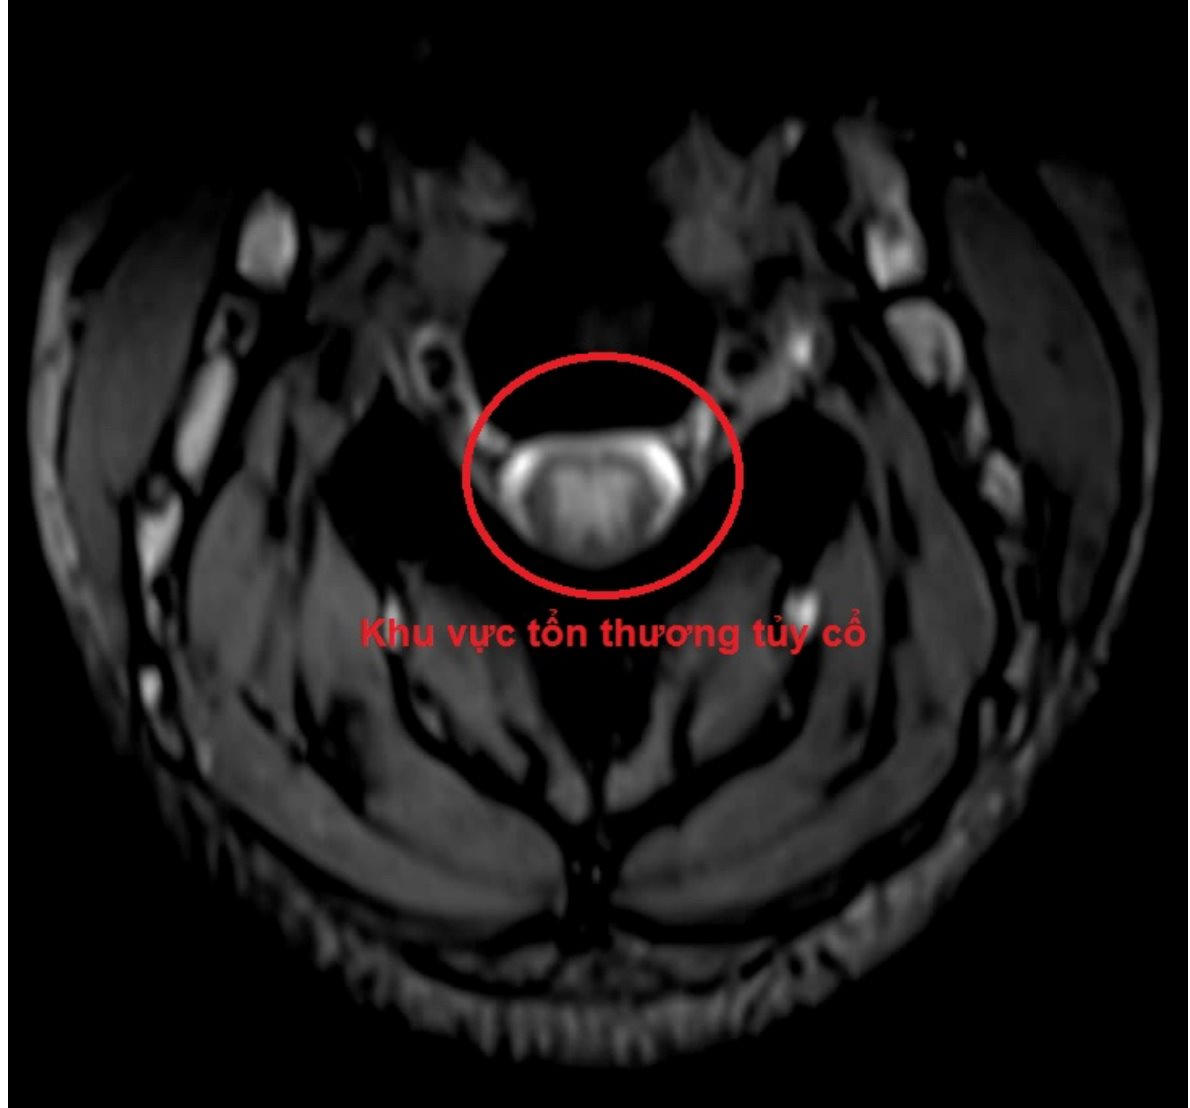

Chính vì vậy, trên những người bệnh có triệu chứng tê bì, dị cảm tứ chi, việc khai thác tiền sử lạm dụng bóng cười, khám lâm sàng và cận lâm sàng đầy đủ, đặc biệt là MRI cột sống cổ và đo dẫn truyền thần kinh sẽ giúp cho việc chẩn đoán chính xác. Từ đó sẽ phục hồi chức năng vận động của người bệnh một cách tối đa.